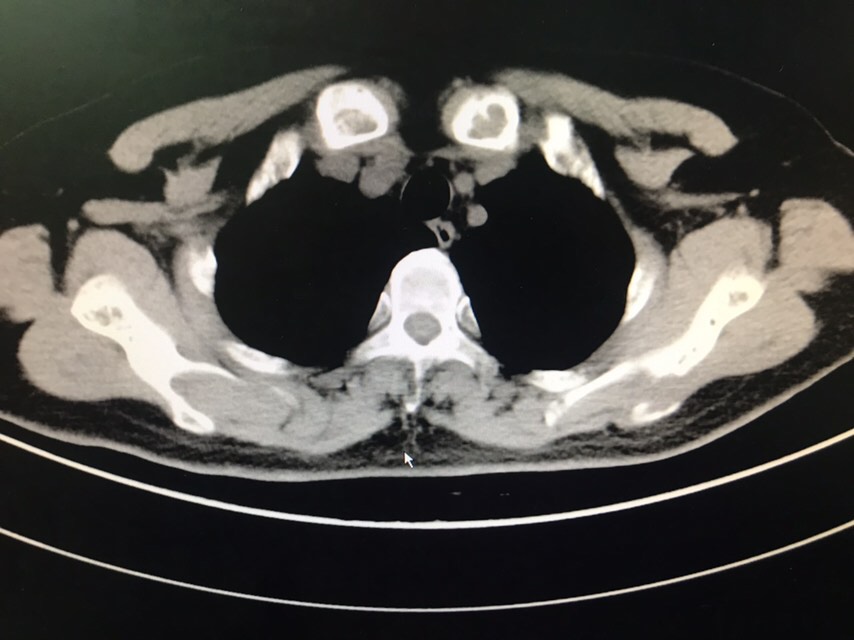

查体无特殊。辅助检查:PET-CT:1、部分颅骨、部分颅底骨质、双侧下颌骨、双侧肩胛骨、双侧锁骨、双侧肱骨上段、双侧多肋骨、胸骨、双侧髂骨、骶1棘突、双侧耻骨部分骨质虫蚀样、溶骨样破坏伴部分破坏骨质FDG代谢异常增高;上述改变考虑多发性骨髓瘤可能性大,请结合临床或右侧肋骨病灶活检。2、甲状腺右叶稍低密度结节影,无FDG代谢异常增高,多为良性病变,建议专科检查;3、双侧口咽壁对称性FDG增高,无确切占位征象,考虑为炎性改变;4、右肾错构瘤;5、脊柱部分骨质增生。骨髓涂片:目前BM示原始浆细胞比例增高8%,成熟红细胞呈缗钱状排列。骨髓活检:取材骨髓组织增生较低下,三系细胞增生均较低。骨髓流式:标本中若表达CD28,不表达CD19、CD117、cLambda、CD27、CD81、CD20、CD45,符合浆细胞肿瘤表型,正常浆细胞占有核细胞娥0.16%;流式检测中浆细胞易被破坏,比例可能低于形态学,请结合形态及免疫固定电泳结果。免疫球蛋白定量:IgG 12.6g/L,IgA 2.05g/L,IgM 0.94g/L,IgE 5.0g/L。血清固定电泳:未见IgG、IgA、IgM、KAP轻链、LAM轻链单克隆成分。尿固定电泳:在LAM区可见一条单克隆KAP轻链成分。血清游离轻链:游离KAP轻链 3800mg/L,游离LAM轻链16.00mg/L、游离KAP轻链/LAM轻链 237.5,尿游离轻链:游离LAM轻链 4100mg/L,游离LAM轻链9.13mg/L、游离KAP轻链/LAM轻链 449.069。